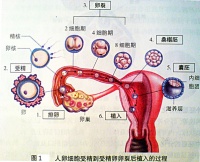

人的受精作用是在输卵管的上段完成。当受精卵在输卵管中段时,胚胎发育就开始了。受精卵一边进行卵裂,一边沿输卵管向子宫方向下行,2~3天可到达子宫。那时的胚胎是由许多细胞构成的中空的小球体,称为胚泡。

受精后约一周,胚泡植入增厚的子宫内股中,这就称为妊娠。胚泡不断通过细胞分裂和细胞的分化而长大,分成了两部分。一部分是胚胎本身将来发育成胎儿;另一部分演变为胚外膜,最重要的是羊膜、胎盘和脐带,胎儿通过胎盘和母体进行物质交换。

直接发育和间接发育,作为两种模式,虽能够概括所有多细胞动物的胚胎发育,但还不足以表达出无脊椎动物各门类胚胎发育的特点及其相互联系。各门无脊椎动物的后期胚胎发育或变态期的形态发生过程,都各具发展方向,当然难以归纳为少数模式。但如以早期胚胎发育过程为准,则无论在进化水平相近门类之间或不同进化水平门类之间,都存在着一些形态发生上的共性或规律性的内容。这方面内容不仅体现着个体发育与系统发育间相互制约关系,体现着进化地位的高低,也体现着亲缘关系的远近。20世纪40年代以来,以上内容已成为确定各门无脊椎动物分类位置和说明其进化方向的重要依据,因而这里也以之试作建立无脊椎动物胚胎发育基本模式的理论基础。下述几种胚胎发育基本模式除原生动物模式和两胚层动物模式外,其他几种模式与分类上无体腔动物、假体腔动物、裂腔动物和腔肠动物的划分是一致的。 人的受精作用是在输卵管的上段完成。当受精卵在输卵管中段时,胚胎发育就开始了。受精卵一边进行有丝分裂,一边沿输卵管向子宫方向下行,2~3天可到达子宫。那时的胚胎是由许多细胞构成的中空的小球体,称为胚泡。

受精后约一周,胚泡植入增厚的子宫内股中,这就称为妊娠。胚泡不断通过细胞分裂和细胞的分化而长大,分成了两部分。一部分是胚胎本身将来发育成胎儿;另一部分演变为胚外膜,最重要的是羊膜、胎盘和脐带,胎儿通过胎盘和母体进行物质交换。

受精卵一旦形成,随即启动卵裂机制。在第3、4天时受精卵已分裂为约

100个细胞的内细胞团。经输卵管蠕动细胞团被送入子宫腔,通过表面粘性物,贴附与子宫内膜,靠近子宫内膜的细胞分泌一种酶,将子宫内膜细胞裂解,形成一个小洞,从受精后的5、6天开始至第11、12天,整个胚泡埋入内膜,该过程称为"着床"或"植入"(图1-6)。胚泡植入后,子宫内膜重新长好,胚泡表面的滋养层细胞不断分裂,长出绒毛状突起,形成许多绒毛,伸入子宫内膜,吸收母体营养(图1)。